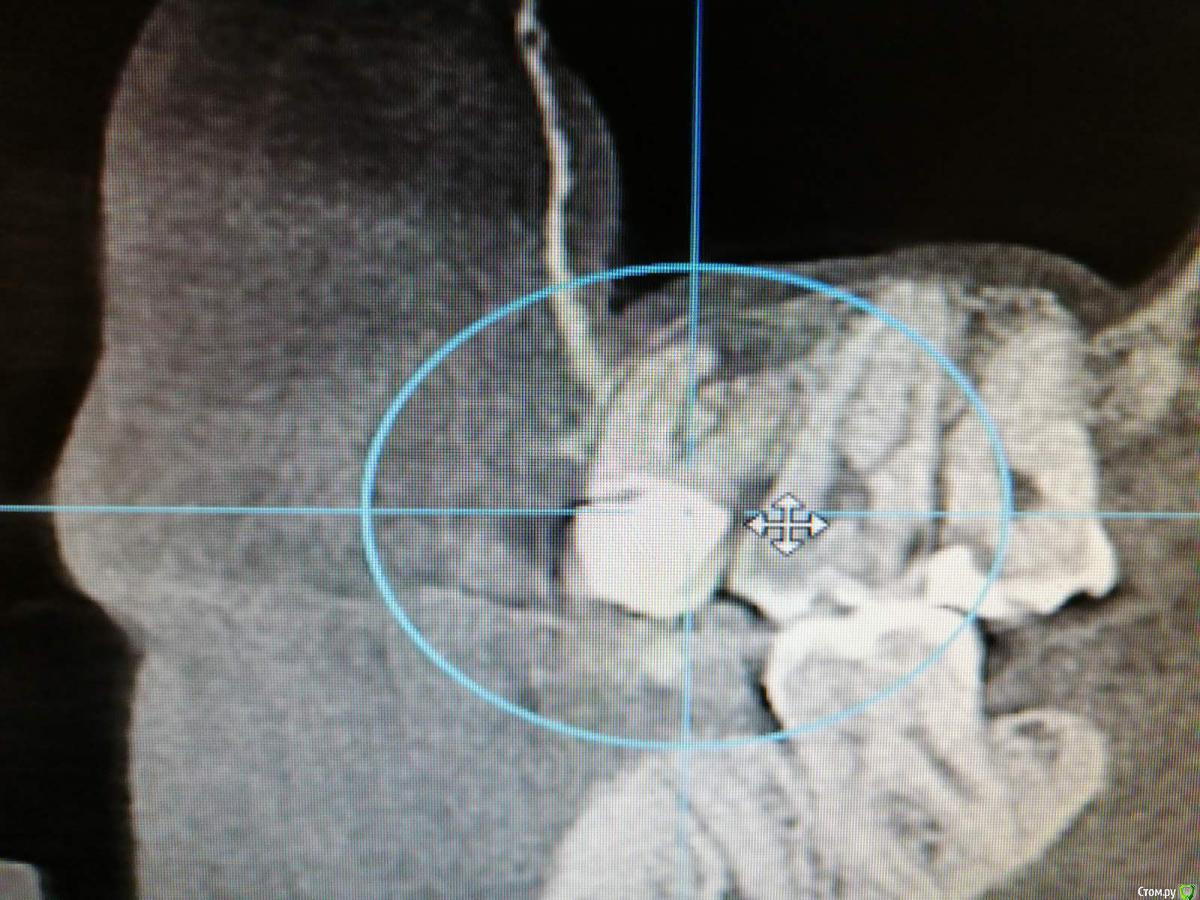

Добрый день. Встал вопрос об имплантации. Были удалены 5 и 6 зубы верхней челюсти. После удаления ничего не беспокоило. Все затянулось десной. через 3 мес. новое КТ. На снимке видно твердое тело в гайморовой пазухе. Врач(не тот который удалял) сказала, что мне надо обращаться к лору. Посоветуйте что делать? Меня не беспокоит челюсть. Дышу я хорошо.

Никаких ощущений нет плохих. Можно будет обойтись без госпитализации? Первый снимок до удаления и два спустя 3 мес после удаления.